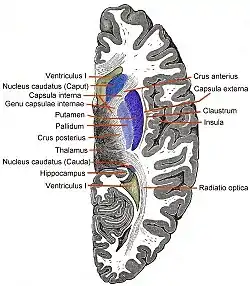

Coronal section of brain immediately in front of pons. (Insula labeled at upper right.) | |

The insula of the left side, exposed by removing the opercula. Coronal section through anterior cornua of lateral ventricles.

Coronal section through anterior cornua of lateral ventricles. Horizontal section of left cerebral hemisphere.